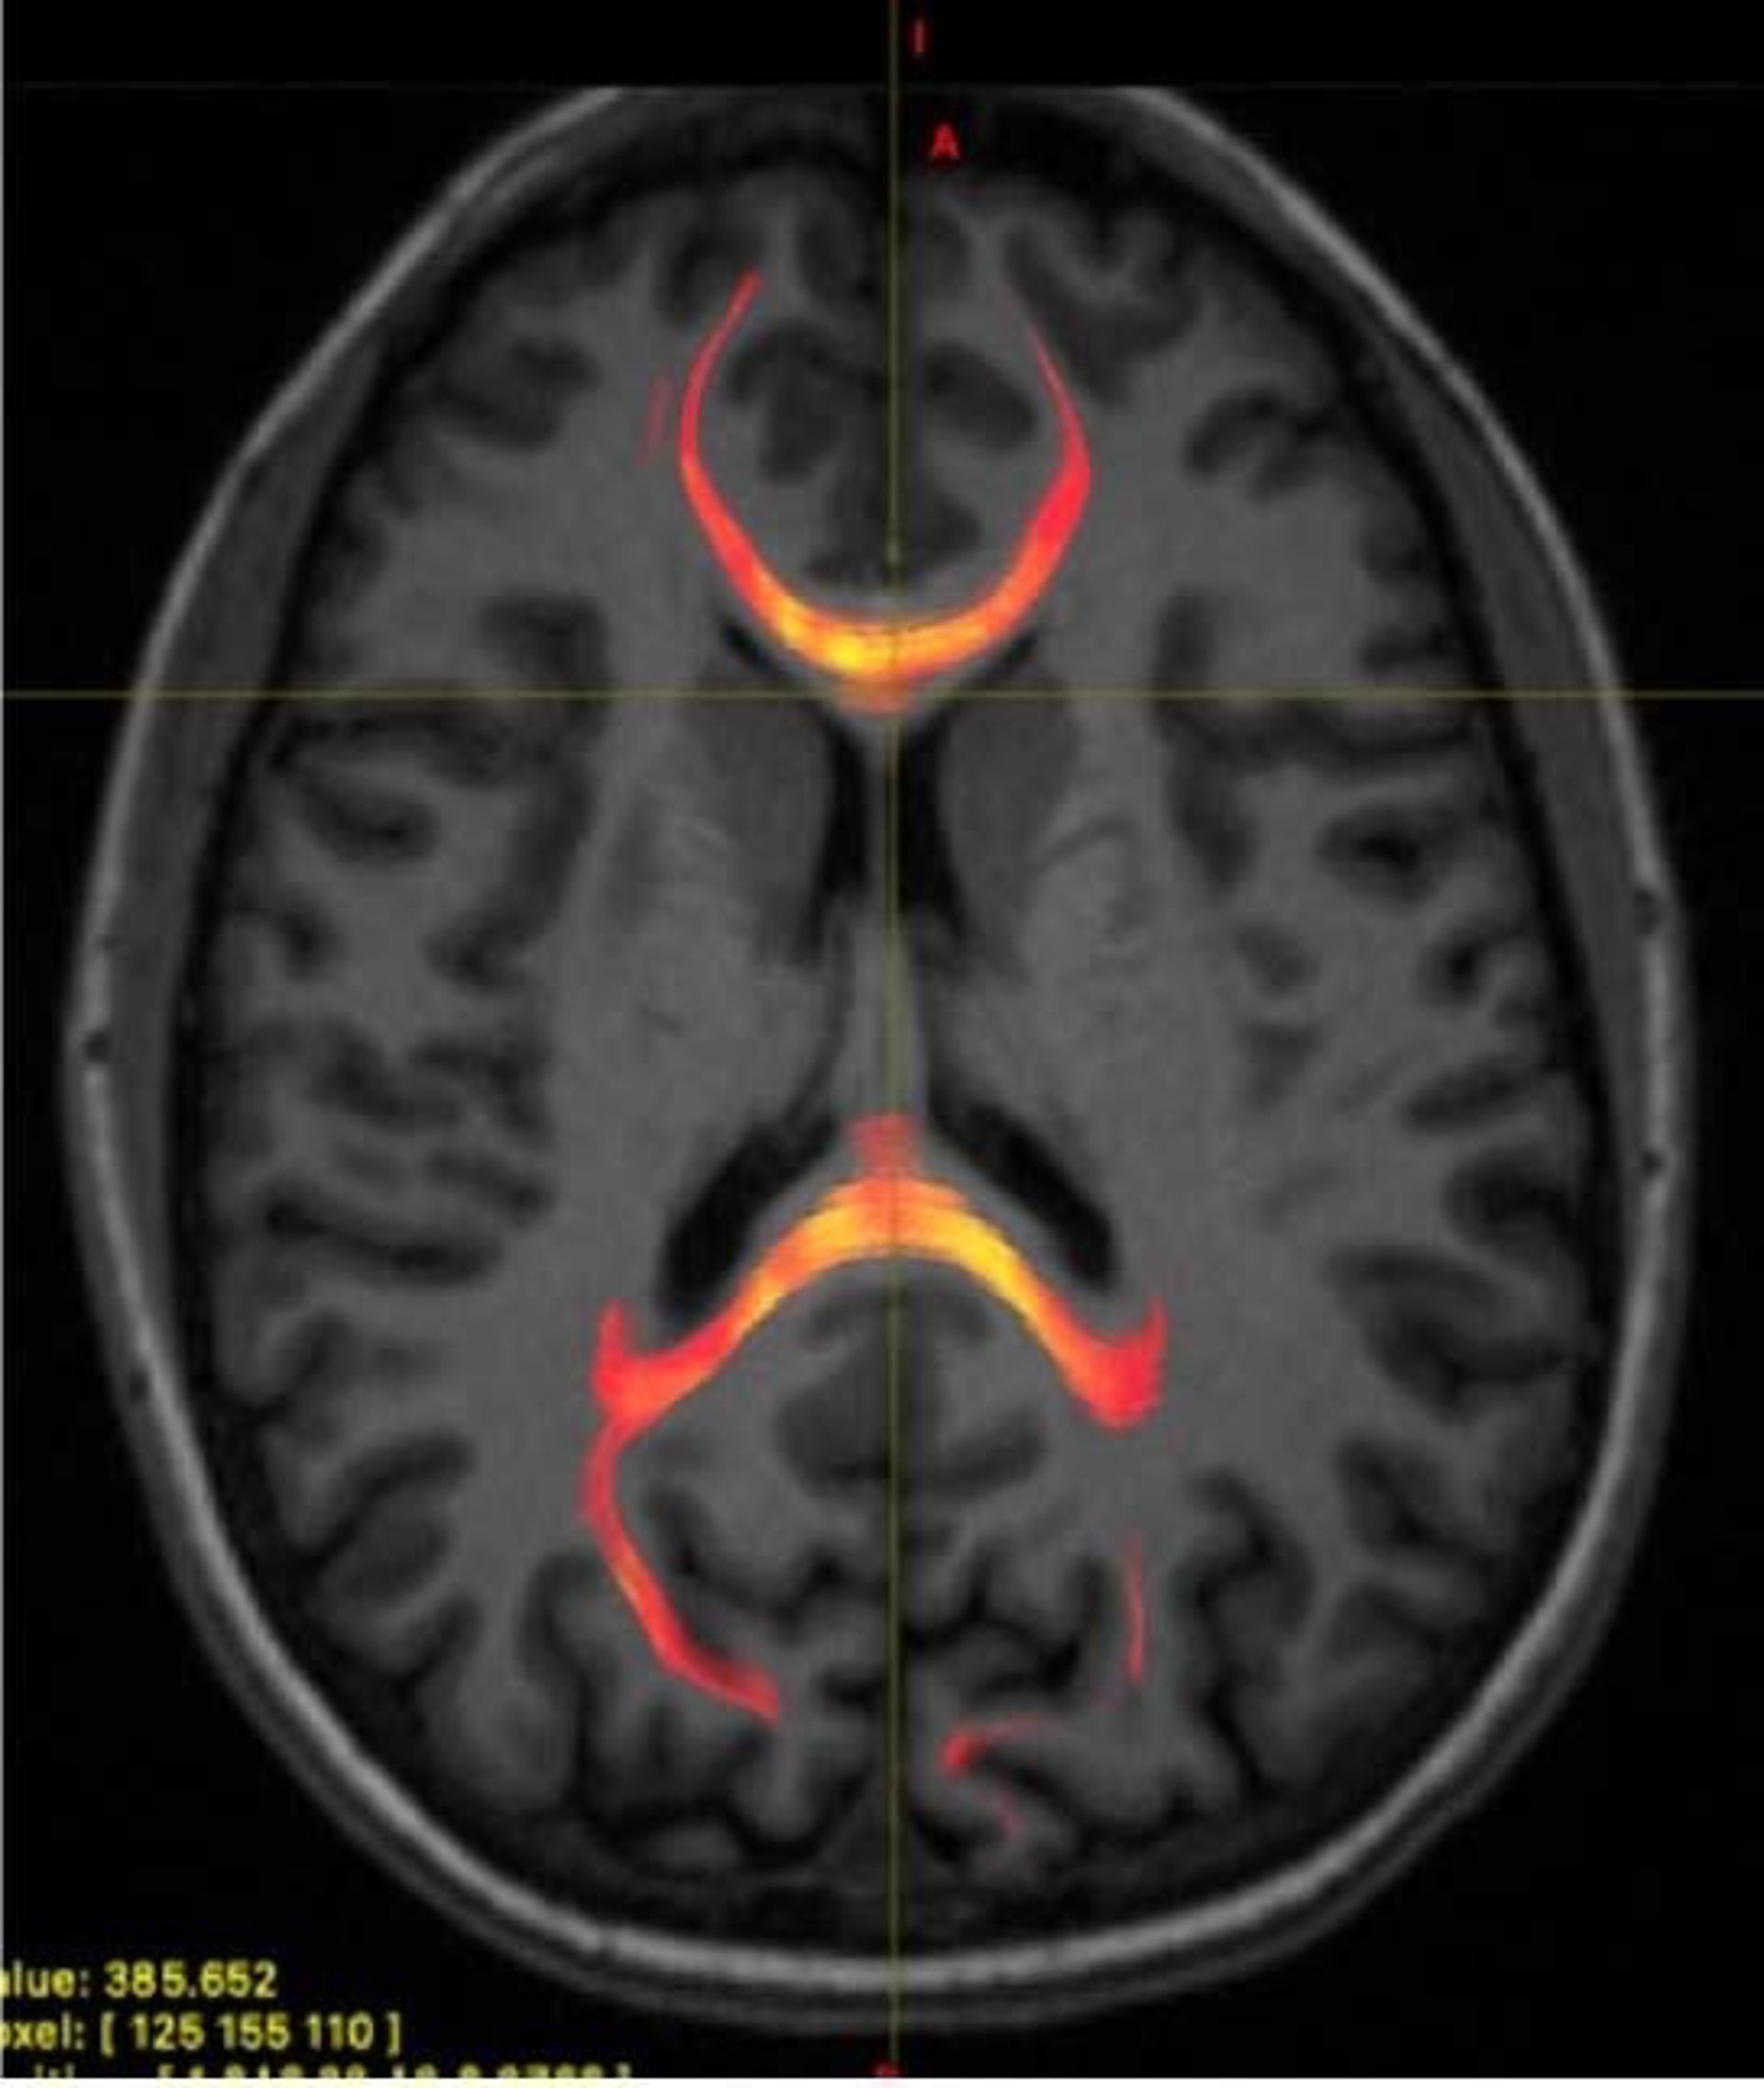

Imagen de RMN de un paciente con lesión cerebral traumática leve que muestra tractografía de fibra callosa del cuerpo

Imagen de RMN de un paciente con lesión cerebral traumática leve que muestra tractografía de fibra callosa del cuerpo - RSNA

Para intenter conseguir más información, investigadores de la Facultad de Medicina de la Universidad de Nueva York (Estados Unidos) compararon la condición del cuerpo calloso en 36 pacientes con conmoción cerebral reciente con la de 27 personas sanas. Estudiaron los cerebros de los participantes con dos avances innovadores, incluyendo una técnica de resonancia magnética (RM) que usa medidas de difusión de agua para proporcionar una vista microscópica de la materia blanca que transporta la señal del cerebro.